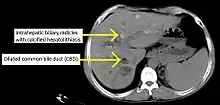

PSC is characterized by inflammation of the bile ducts (cholangitis) with consequent stricturing (i.e., narrowing) and hardening (sclerosis) of these ducts due to scar formation, be it inside and/or outside the liver.[17] The resulting scarring of the bile ducts obstructs the flow of bile, which further perpetuates bile duct and liver injury. Chronic impairment of bile flow due to blockage and dysfunctional bile transport (cholestasis) causes progressive biliary fibrosis and ultimately biliary cirrhosis and liver failure.[18]

Historically, a cholangiogram would be obtained via endoscopic retrograde cholangiopancreatography (ERCP), which typically reveals "beading" (alternating strictures and dilation) of the bile ducts inside and/or outside the liver. Currently, the preferred option for diagnostic cholangiography, given its noninvasive yet highly accurate nature, is magnetic resonance cholangiopancreatography (MRCP), a magnetic resonance imaging technique. MRCP has unique strengths, including high spatial resolution, and can even be used to visualize the biliary tract of small animal models of PSC.[19]